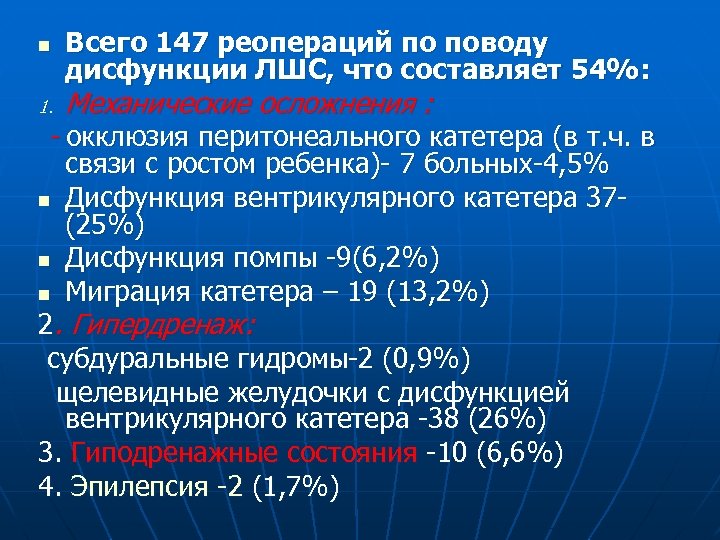

n 1. Всего 147 реопераций по поводу дисфункции ЛШС, что составляет 54%: Механические осложнения : - окклюзия перитонеального катетера (в т. ч. в n n n связи с ростом ребенка)- 7 больных-4, 5% Дисфункция вентрикулярного катетера 37 - (25%) Дисфункция помпы -9(6, 2%) Миграция катетера – 19 (13, 2%) 2. Гипердренаж: субдуральные гидромы-2 (0, 9%) щелевидные желудочки с дисфункцией вентрикулярного катетера -38 (26%) 3. Гиподренажные состояния -10 (6, 6%) 4. Эпилепсия -2 (1, 7%)